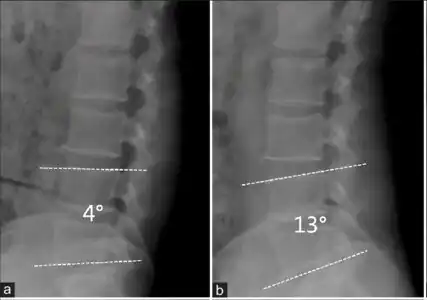

Forward displacement of a proximal vertebra in relation to its adjacent vertebra in association with an intact neural arch, and in the presence of degenerative changes, is known as degenerative spondylolisthesis,[10][11] which narrows the spinal canal, and symptoms of spinal stenosis are common. Of these, neural claudication is most common. Any forward slipping of one vertebra on another can cause spinal stenosis by narrowing the canal. If this forward slipping narrows the canal sufficiently, and impinges on the contents of the spinal column, it is spinal stenosis by definition. If associated symptoms of narrowing exist, the diagnosis of spinal stenosis is confirmed. With increasing age, the occurrence of degenerative spondylolisthesis becomes more common. The most common spondylolisthesis occurs with slipping of L4 on L5. Frymoyer showed that spondylolisthesis with canal stenosis is more common in diabetic women who have undergone oophorectomy (removal of ovaries). The cause of symptoms in the legs can be difficult to determine. A peripheral neuropathy secondary to diabetes can have the same symptoms as spinal stenosis.[12]